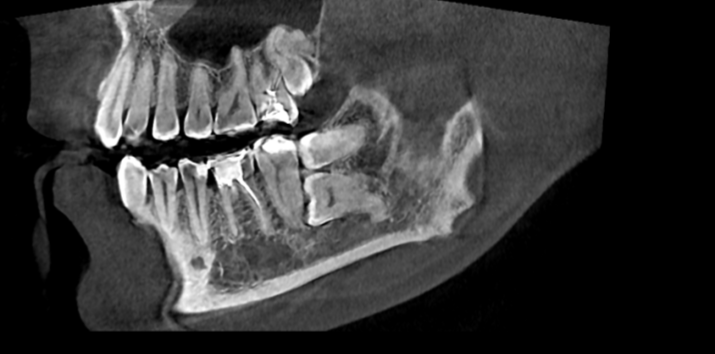

Вот такие коварные восьмые, а иногда и девятые маляры залегают в толщи кости.

Как происходит процесс удаления зуба мудрости? В первую очередь перед процедурой наш дантист сделает рентген, чтобы определить местоположение и особенности строения зуба. Сама операция проходит под местной анестезией, и мы Вас уверяем что Вы даже не почувствуете укола. При прорезовшемся зубе после действия обезболивающего врач при помощи специальных инструментов извлечет зуб и наложит швы. Длится такая операция несколько минут , но стоит заметить, что верхние восьмерки как правило удаляются быстрее, потому что у нижних зубов корни имеют менее крепкую и извилистую структуру.

У пациентов, помимо прорезыванных зубов мудрости, встречаются и так называемые ретинированные, это те которые полностью скрыты под десной, а также дистопированные - с неправильным расположением в зубном ряду. Чаще всего встречаются ретенированные и дистопированные зубы одновременно. Следует также выделить полуретинированные восьмерки - это зубы , которые появились из десны не до конца. Зачастую в том варианте, когда видна только часть зуба, между ним и десной образуется небольшой карман- капюшон, и это образование вызывает гнойное воспаление - перикоронит. В запущенных случаях, помимо болевых ощущений в самой зоне зуба перикоронит может вызывать сильнейшие головные боли и повышение температуры.

В

задней области верхней челюсти, замена зуба с

помощью зубных имплантатов, зачастую, требует хирургической операции по пазухе.

Эта операция представляет собой форму предварительной протезной

хирургии для повышения качества и количества кости в задней области

верхней челюсти. Предварительная оценка верхней челюсти необходима для успеха этой операции.

Если количество костей, между гребнем и полостью, является недостаточным, (<5 мм), то необходима процедура открытого синусового подъема ( синус лифтинг).

В представленном случае была сделана , как раз такая операция на верхней челюсти перед установкой имплантов.